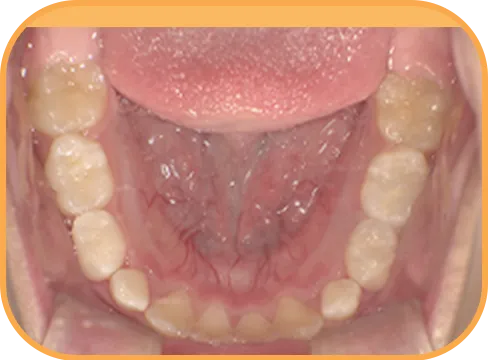

• 下 顎

治療前下顎からの歯の様子

治療後下顎からの歯の様子